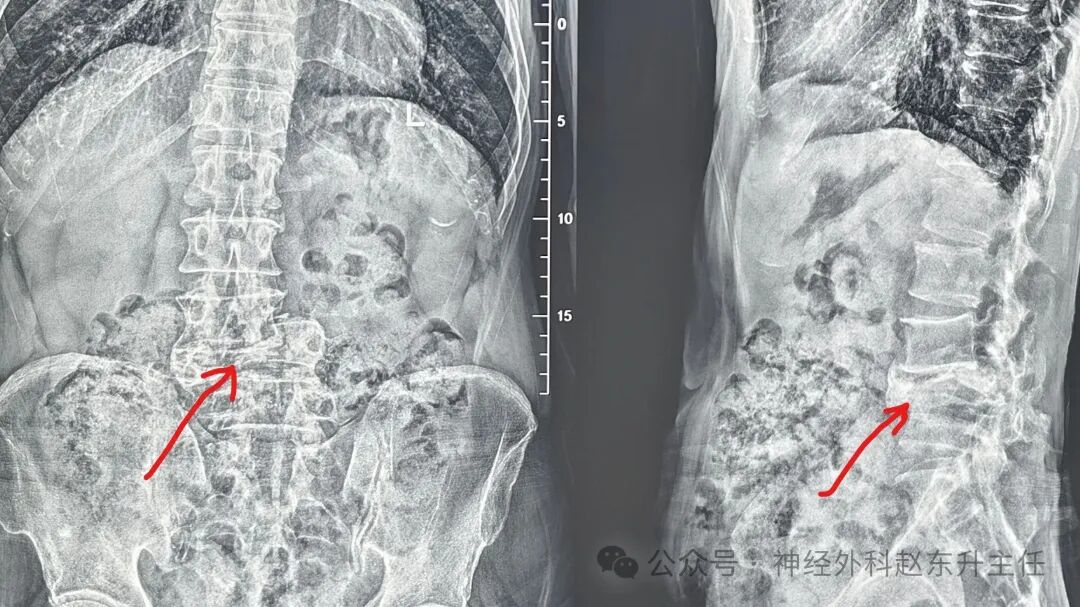

1.jpg术前X线提示腰椎滑脱

2.jpg腰椎CT提示腰椎滑脱伴骨折